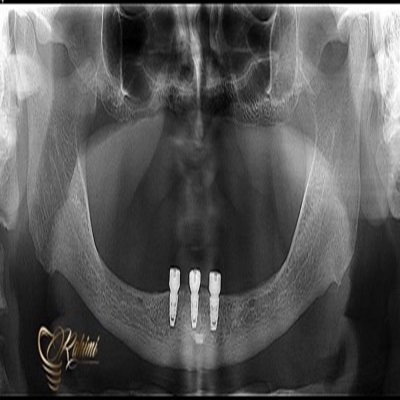

دکتر حامد رحیمی

دکتر حامد رحیمی متولد سال ۱۳۶۷ می باشند.ایشان در سال ۱۳۸۵ موفق به ورود به رشته دندانپزشکی دانشگاه علوم پزشکی تهران شدند و در سال ۱۳۹۱ فارغ التحصیل گردیدند.در سال ۱۳۹۴ پس از گذراندن طرح دوره دکتری عمومی در استان قم موفق به قبولی در رشته جراحی لثه و ایمپلنت دانشکاه علوم پزشکی تهران گردیدند.ایشان از سال ۱۳۹۷ و پس از کسب بورد تخصصی به عنوان عضو هیات علمی دانشگاه علوم پزشکی قم مشغول هستند.